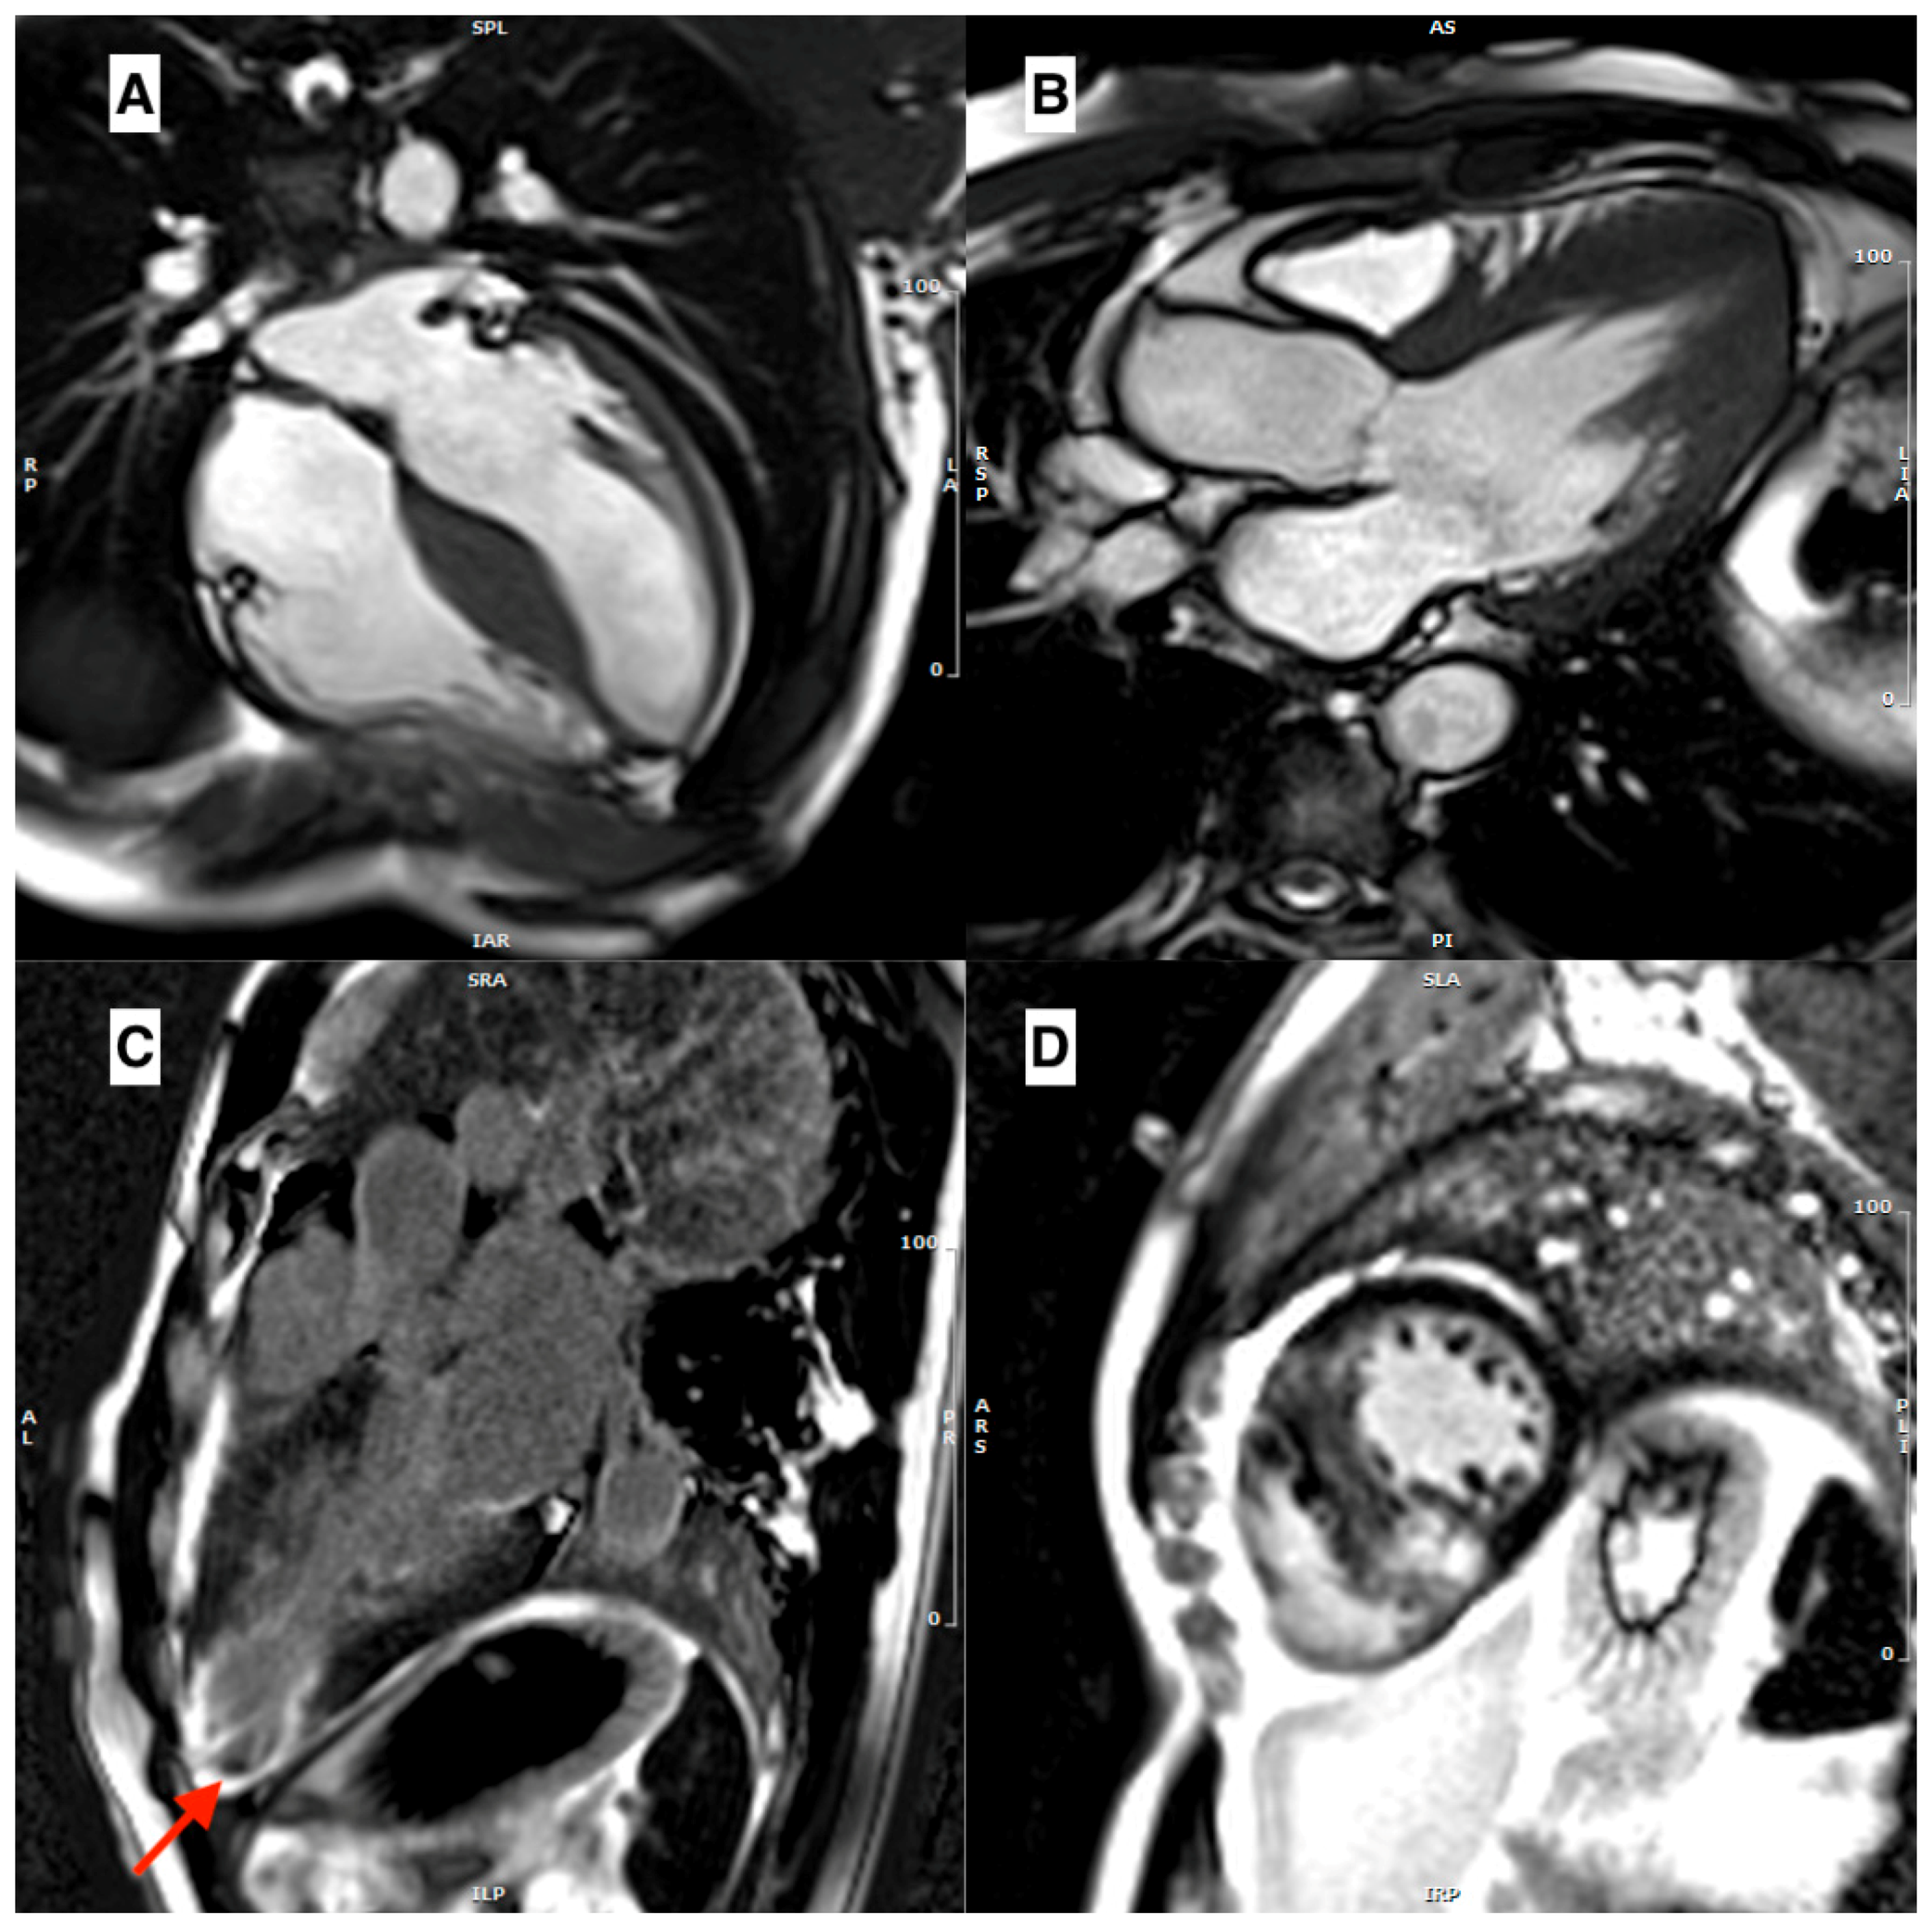

3.1. Morpho-Functional Features in Hypertrophic Phenotypes

- Maron, M.S.; Maron, B.J.; Harrigan, C.; Buros, J.; Gibson, C.M.; Olivotto, I.; Biller, L.; Lesser, J.R.; Udelson, J.E.; Manning, W.J.; et al. Hypertrophic Cardiomyopathy Phenotype Revisited After 50 Years With Cardiovascular Magnetic Resonance. J. Am. Coll. Cardiol. 2009, 54, 220–228. [Google Scholar] [CrossRef]

- Moon, J.C.C.; Fisher, N.G.; McKenna, W.J.; Pennell, D.J. Detection of apical hypertrophic cardiomyopathy by cardiovascular magnetic resonance in patients with non-diagnostic echocardiography. Heart 2004, 90, 645–649. [Google Scholar] [CrossRef]

- Maron, M.S.; Finley, J.J.; Bos, J.M.; Hauser, T.H.; Manning, W.J.; Haas, T.S.; Lesser, J.R.; Udelson, J.E.; Ackerman, M.J.; Maron, B.J. Prevalence, Clinical Significance, and Natural History of Left Ventricular Apical Aneurysms in Hypertrophic Cardiomyopathy. Circulation 2008, 118, 1541–1549. [Google Scholar] [CrossRef]

- Cui, L.; Tse, G.; Zhao, Z.; Bazoukis, G.; Letsas, K.P.; Korantzopoulos, P.; Roever, L.; Li, G.; Liu, T. Mid-ventricular obstructive hypertrophic cardiomyopathy with apical aneurysm: An important subtype of arrhythmogenic cardiomyopathy. Ann. Noninvasive Electrocardiol. 2019, 24, e12638. [Google Scholar] [CrossRef] [PubMed]

- Maron, M.S.; Hauser, T.H.; Dubrow, E.; Horst, T.A.; Kissinger, K.V.; Udelson, J.E.; Manning, W.J. Right Ventricular Involvement in Hypertrophic Cardiomyopathy. Am. J. Cardiol. 2007, 100, 1293–1298. [Google Scholar] [CrossRef]

- Maron, M.S.; Rowin, E.J.; Lin, D.; Appelbaum, E.; Chan, R.H.; Gibson, C.M.; Lesser, J.R.; Lindberg, J.; Haas, T.S.; Udelson, J.E.; et al. Prevalence and Clinical Profile of Myocardial Crypts in Hypertrophic Cardiomyopathy. Circ. Cardiovasc. Imaging 2012, 5, 441–447. [Google Scholar] [CrossRef]

- Captur, G.; Lopes, L.R.; Mohun, T.J.; Patel, V.; Li, C.; Bassett, P.; Finocchiaro, G.; Ferreira, V.M.; Esteban, M.T.; Muthurangu, V.; et al. Prediction of Sarcomere Mutations in Subclinical Hypertrophic Cardiomyopathy. Circ. Cardiovasc. Imaging 2014, 7, 863–871. [Google Scholar] [CrossRef]

- Maron, M.S.; Olivotto, I.; Harrigan, C.; Appelbaum, E.; Gibson, C.M.; Lesser, J.R.; Haas, T.S.; Udelson, J.E.; Manning, W.J.; Maron, B.J. Mitral Valve Abnormalities Identified by Cardiovascular Magnetic Resonance Represent a Primary Phenotypic Expression of Hypertrophic Cardiomyopathy. Circulation 2011, 124, 40–47. [Google Scholar] [CrossRef]

- Harrigan, C.J.; Appelbaum, E.; Maron, B.J.; Buros, J.L.; Gibson, C.M.; Lesser, J.R.; Udelson, J.E.; Manning, W.J.; Maron, M.S. Significance of Papillary Muscle Abnormalities Identified by Cardiovascular Magnetic Resonance in Hypertrophic Cardiomyopathy. Am. J. Cardiol. 2008, 101, 668–673. [Google Scholar] [CrossRef]